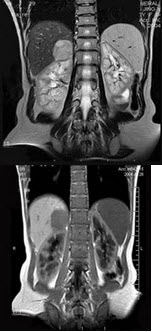

男,31岁,体检时超声发现右肾上腺区病灶,MRI扫描如图所示,下列说法正确的是( )

A:右侧肾上腺区可见一类圆形病灶,与周围组织分界清楚

B:该病灶在T1WI为等信号,在T2WI为稍高信号

C:考虑为右侧肾上腺腺瘤

D:考虑为右侧肾上腺髓样脂肪瘤

E:考虑为右侧肾上腺嗜铬细胞瘤